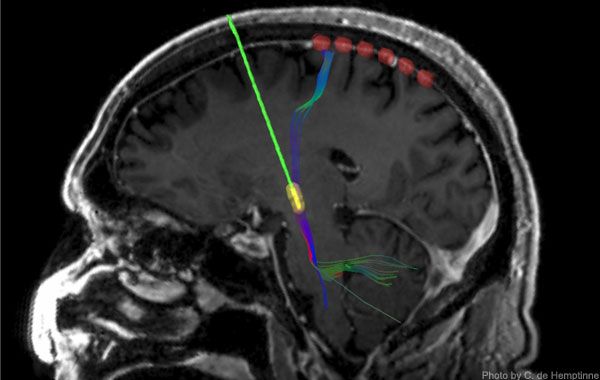

RM de donde se aprecia la actividad cortical y un electrodo de estimulación cerebral profunda (verde con punta amarilla). C. DE HEMOTINNE – ABC